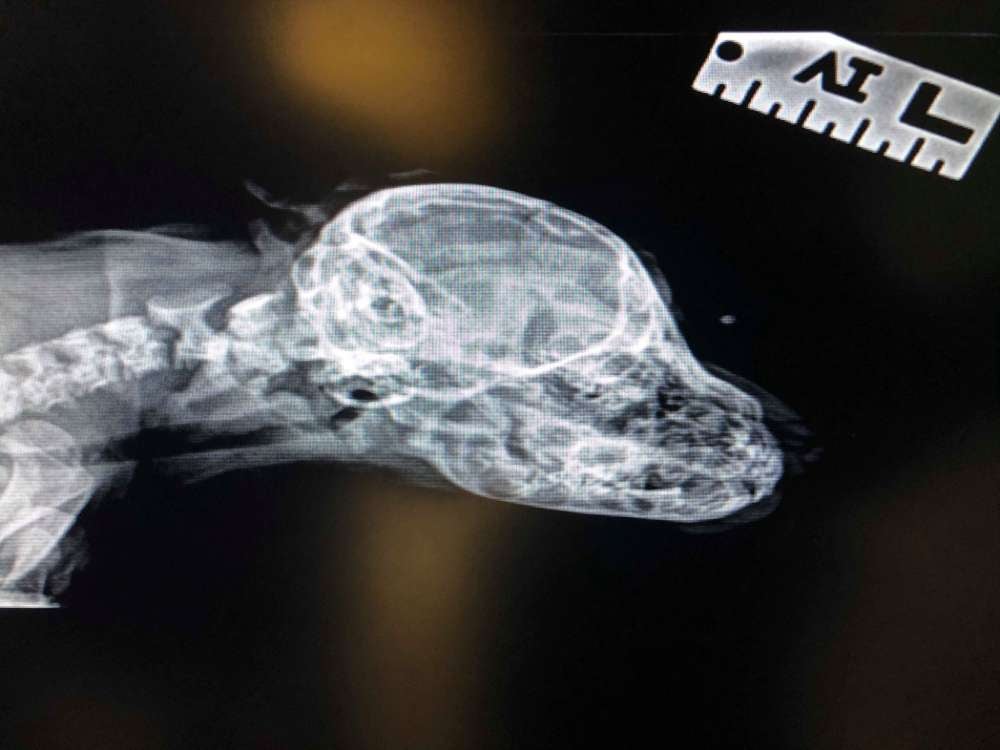

Tras ser rescatado lo llevaron a un veterinario para que le hicieran un chequeo. El médico también realizó radiografías del cachorro en un intento por descubrir el misterio de su característica única en la frente. Si bien la naturaleza del defecto de nacimiento sigue sin estar clara, la cola adicional no representa ningún riesgo aparente para su salud. Según el centro:

La cola en la cara no molesta a Narwhal y actúa como cualquier cachorro normal. La cola extra no está conectada a nada y no tiene un uso real que no sea convertirlo en un perro con su propia personalidad. En este momento, él es el ejemplo increíble más singular de lo que hacemos aquí y estamos muy agradecidos de tener la oportunidad de ser parte de su viaje.